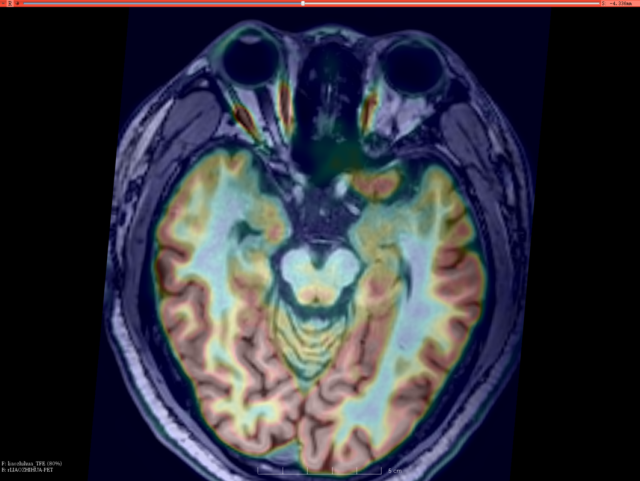

头颅PET-CT&MRI融合:右侧海马代谢降低